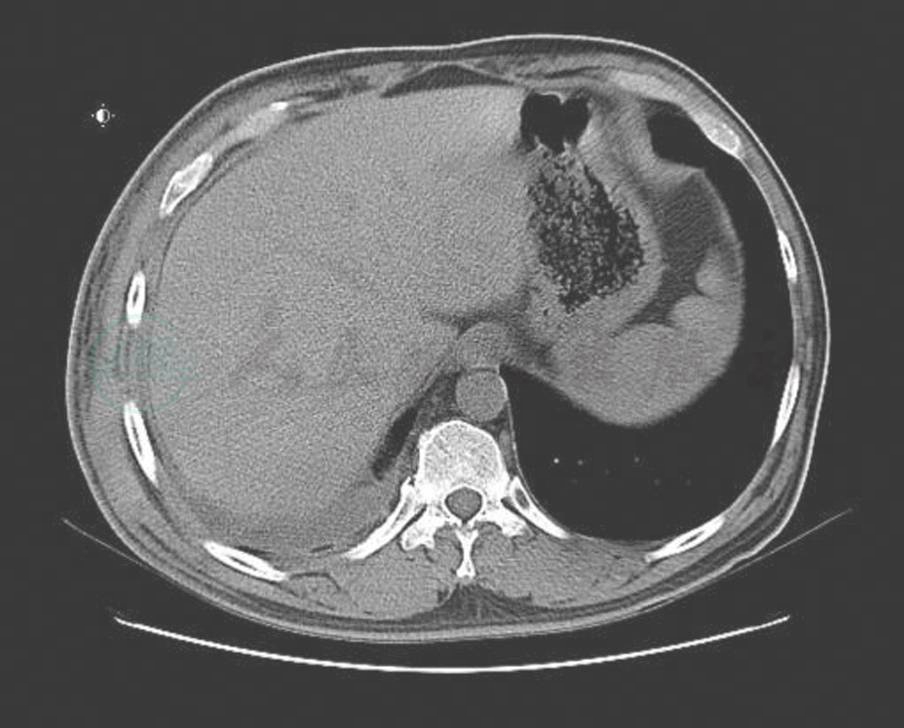

血象、血沉、结核三项、G试验、呼吸道病原及风湿免疫检查均未见异常。T-SPOT阳性。IgG 1410mg/dl,IgG4 355mg/dl。胸腔积液:送检胸水涂片及细胞病理学未见阳性结果;常规生化结果考虑为渗出液。胸部CT:右侧胸壁软组织占位并肋骨破坏及纵隔、腋窝淋巴结多发转移,不除外胸壁来源的恶性肿瘤;双肺炎症(图2、图3、图4)。小器官超声:双侧腋下多发肿大淋巴结。我院病理会诊(外院腋窝淋巴结标本):其内见血管内皮细胞增生显著。我院右侧腋窝淋巴结活检病理:Castleman病(巨大淋巴结增生症),透明血管型。免疫组化染色结果:CD3(T 细胞 +),CD20(B 细胞 +),CD21(+),CD34(血管 +),CD38(+),Ki-67(+25%~50%)。我院病理会诊(外院胸壁皮肤标本):考虑血管源性肿瘤,以上皮样血管内皮细胞瘤可能性大。我院右胸腹部皮肤活检:不除外血管肉瘤。北京协和医院病理会诊:(外院淋巴结):淋巴结结构存在,淋巴滤泡生发中心缩小,滤泡间见较多浆细胞浸润伴小血管增生。(外院皮肤):真皮胶原纤维及小血管显著增生,伴少许淋巴细胞浆细胞浸润;结合免疫组化考虑为IgG4相关性疾病,建议结合临床并作相关检查及测定血清IgG4水平。(我院淋巴结):CD138(+)、CD38(+)、IgG4/IgG(大于 40%)、IgG4(100 个 /HPF)。(我院皮肤):CD138(+)、CD38(+)、IgG45、IgG4(100 个 /HPF)。诊断考虑:淋巴结:Castleman disease。皮肤:不除外高分化血管肉瘤。

图4 治疗前(淋巴结)

入院后完善相关检查,给予增强免疫治疗。4月27日行超声引导下胸腔穿刺引流,共引流出胸水3000ml后拔除引流管。我院病理科会诊患者外院病理切片,考虑上皮样血管内皮瘤可能性大。患者于4月28日取右侧胸壁皮肤活检,病理回报为不除外血管肉瘤。5月7日在局麻下行右侧腋窝淋巴结活检,病理回报Castleman病,透明血管型。后于5月19日将我院皮肤、腋窝淋巴结病理切片送协和病理科会诊,考虑IgG4相关性疾病,建议完善相关血清学检查。完善IgG、IgG4检查,并于5月26日请全院联合会诊,综合皮肤科、风湿科、CT室、病理科会诊意见,考虑Castleman病合并高分化血管肉瘤可能性大,并于6月9日、6月10日分别行超声引导下淋巴结活检、局麻下皮肤活检,结合我院病理报告及协和医院病理会诊报告进一步考虑为巨大淋巴结增生症(Castleman病)合并高分化血管肉瘤。治疗方面于6月15日开始给予激素治疗:醋酸泼尼松片 40mg 口服 1次/日,同时给予护胃、降糖等治疗,病情稳定后出院,1月后来院复查,肺部CT(图5、图6、图7)及胸部皮疹(图8)较前明显改善。